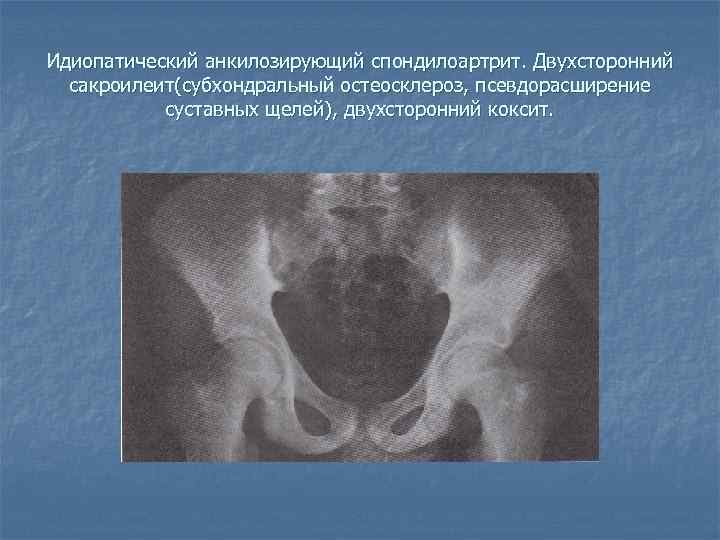

Фотографии и схемы: Коксит правого тазобедренного сустава